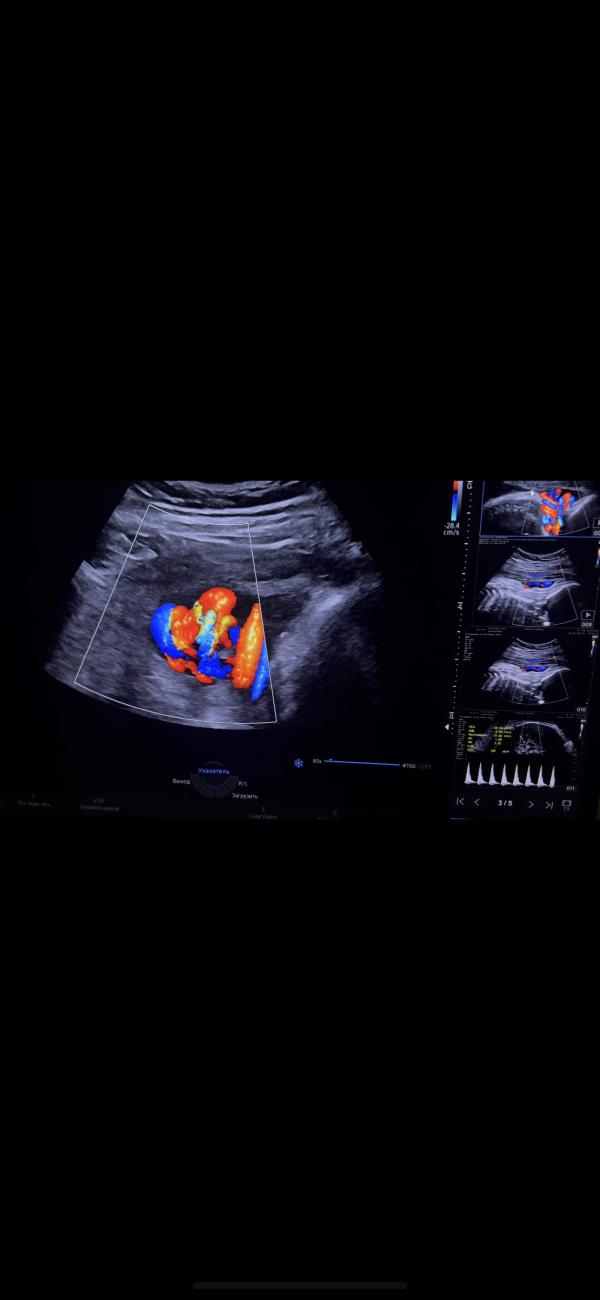

Истинный узел и двойное обвитие: чем опасны?

Истинный узел с двойным обвитием вокруг шеи плода 🤲🏻 🪢